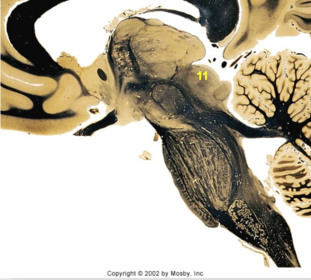

| Head of caudate | |

| Anterior commissure | |

| Thalamus | |

| Substantia nigra | |

| Optic tract | |

| Dentate nucleus | |

| Pons | |

| Longitudinal pontine fibers | |

| Uncus | |

| Superior cerebellar peduncle | |

| Red nucleus | |

| Corticospinal tract (dark) | |

| Pontine nuclei (pale) | |

| Transverse pontine fibers (dark) | |

| Inferior olive | |

| CTT | |

| Medial lemniscus | |

| Nucleus cuneatus | |

| Superior colliculus | |

| Inferior colliculus | |

| Optic nerve | |

| Cerebellum | |

| 4th ventricle | |